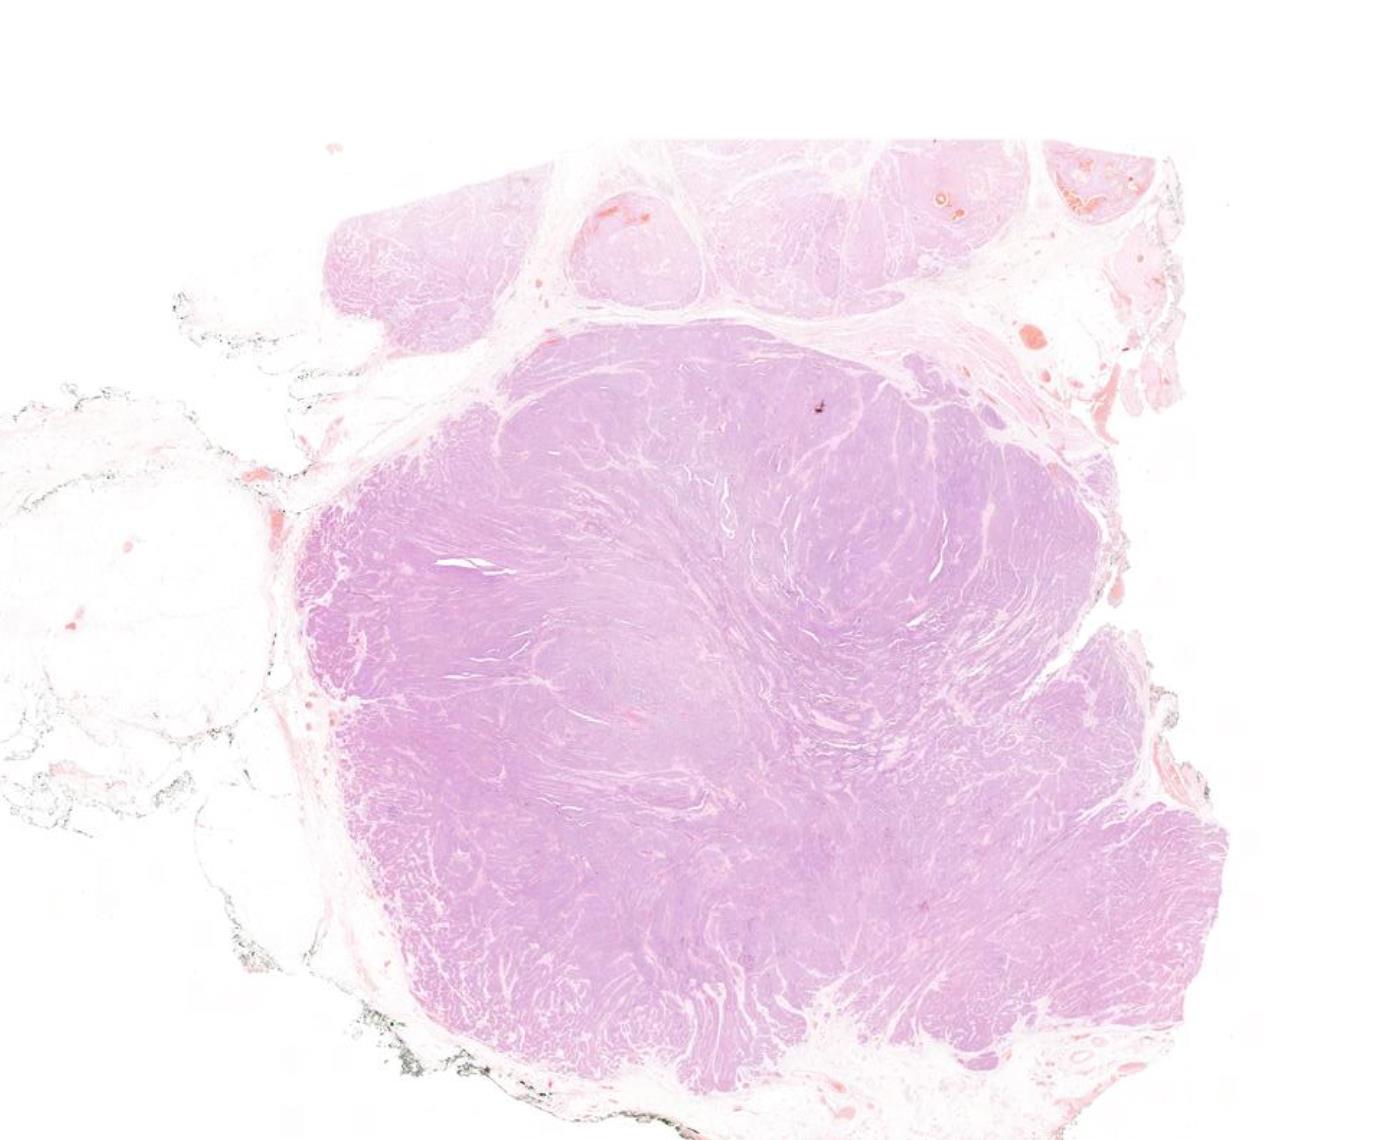

Case 4

42-year-old Female, Left level 4 lymph node.

Case 4 Diagnosis

Metastatic diffuse sclerosing variant of papillary thyroid carcinoma

Diffuse enlargement, Solid tumour nests with squamous metaplasia, including squamous morules, dense sclerosis, numerous psammoma bodies, background chronic lymphocytic thyroiditis This tumour is common in children and young adults BRAF mutation (50%), RET/PTC1 rearrangement (28%), RET/PTC3 (14%) Highlights